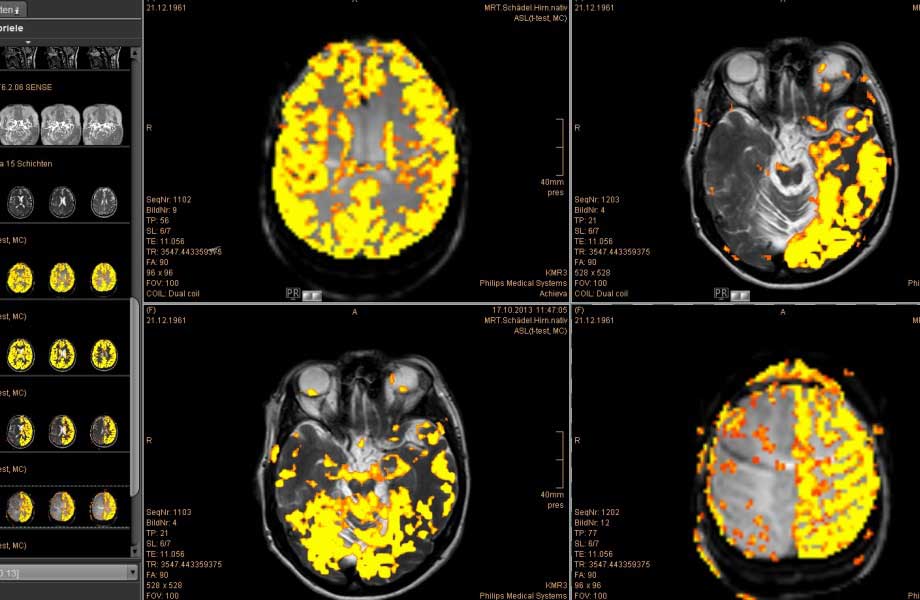

SARS-CoV2-assoziierte Veränderungen der Hirnstruktur im Langzeitverlauf bei nicht-hospitalisierten Personen

SARS-CoV2-assoziierte Veränderungen der Hirnstruktur im Langzeitverlauf bei nicht-hospitalisierten Personen Anhand von Daten der in der prä-Pandemie-Ära begonnenen, longitudinal angelegten „UK Biobank“ konnten erstmals zerebrale MRT-Befunde vor und nach COVID-19 bei denselben Personen erhoben und mit einer Kontrollgruppe Nicht-Infizierter verglichen werden [1]. Im Ergebnis zeigte sich bei ...